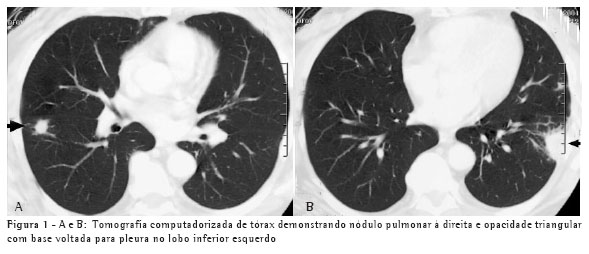

Um paciente, do sexo masculino, branco, de 67 anos, procedente de Blumenau (SC), representante de vendas, iniciou quadro de dispnéia, astenia, dor torácica e sudorese dez dias após limpeza do forro da sua casa, onde estão localizadas caixas d'água. Esteve em contato com fezes de morcego por tempo limitado, enquanto o local era varrido. A presença de nódulos pulmonares em radiografia e tomografia de tórax (Figuras 1A e 1B) e a ausência de expectoração justificaram a realização de biópsia de nódulopulmonar.

conhecimento das síndromes clínicas e a suspeição clínica podem evitar o tratamento empírico. Os achados radiológicos, os exames negativos e a alta freqüência da tuberculose em nosso meio foram os fatores para o tratamento para tuberculose nos dois pacientes. O teste de imunodifusão, embora negativo nestes dois pacientes, tem alta sensibilidade, sendo positivo em aproximadamente 75% dos casos.(6) O tempo de exposição ao inóculo determina a gravidade da doença. Isto explica o fato de o segundo paciente, que varreu o local, ter apresentado uma forma mais grave da doença, com alteração radiológica pulmonar difusa e necessidade de hospitalização. Por outro lado, uma pequena exposição determina lesões pulmonares focais, como no caso 1.